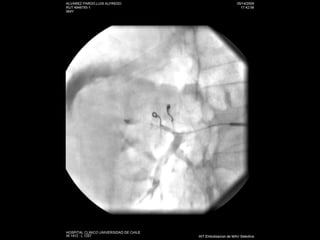

Nefrostomías  Éxito cercano a un 100% Complicaciones 4% hemorragia-infección Inserción anterógrada de catéter doble J

Nefrostomías Éxitocercano a un 100% Complicaciones 4% hemorragia-infección Inserción anterógrada de catéter doble J